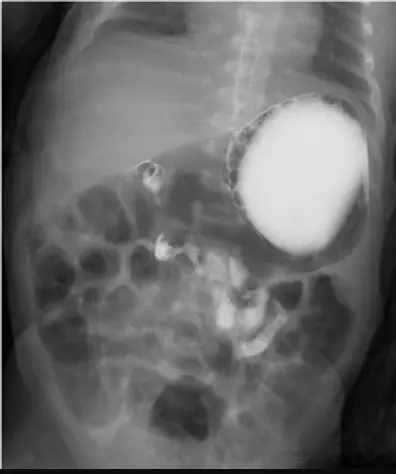

出生兩天大的女嬰因嘔吐不止就醫,接受上消化道攝影結果如圖示,下列何者為最可能之診斷?

提供的上消化道攝影(Upper GI series)影像顯示:

- 顯影劑流向:顯影劑充滿胃部後,順利進入十二指腸。

- 十二指腸路徑異常:正常的十二指腸應該呈現 C 型環繞(C-loop),並橫跨中線至脊椎左側,且十二指腸空腸交界處(DJ junction, Ligament of Treitz)應位於胃幽門水平高度的脊椎左側。

- 螺旋狀徵象(Corkscrew sign):影像中可見十二指腸並未正常跨越中線至左上腹,而是位於脊椎右側或中線處,並呈現螺旋狀向下(spiral or corkscrew appearance) 的形態。這是因為腸繫膜根部過短,導致小腸圍繞著上腸繫膜動脈(SMA)發生扭轉(Volvulus)。

- 影像特徵:上消化道攝影是黃金診斷標準。典型發現為 DJ junction 位置異常(位於脊椎右側或過低)。若合併腸扭轉(Midgut Volvulus),則會出現典型的**「開瓶器徵象」(Corkscrew sign)**,即本題影像所示之螺旋狀小腸迴圈。這是一個外科急症。

患者為出生兩天的新生兒,出現持續嘔吐,上消化道攝影顯示十二指腸未跨越中線,且呈現典型的**「開瓶器徵象」(Corkscrew sign),這是中腸旋轉不良合併中腸扭轉(Midgut Malrotation with Volvulus)** 的特異性影像表現。因此最可能的診斷為 (A) 中腸旋轉不良。